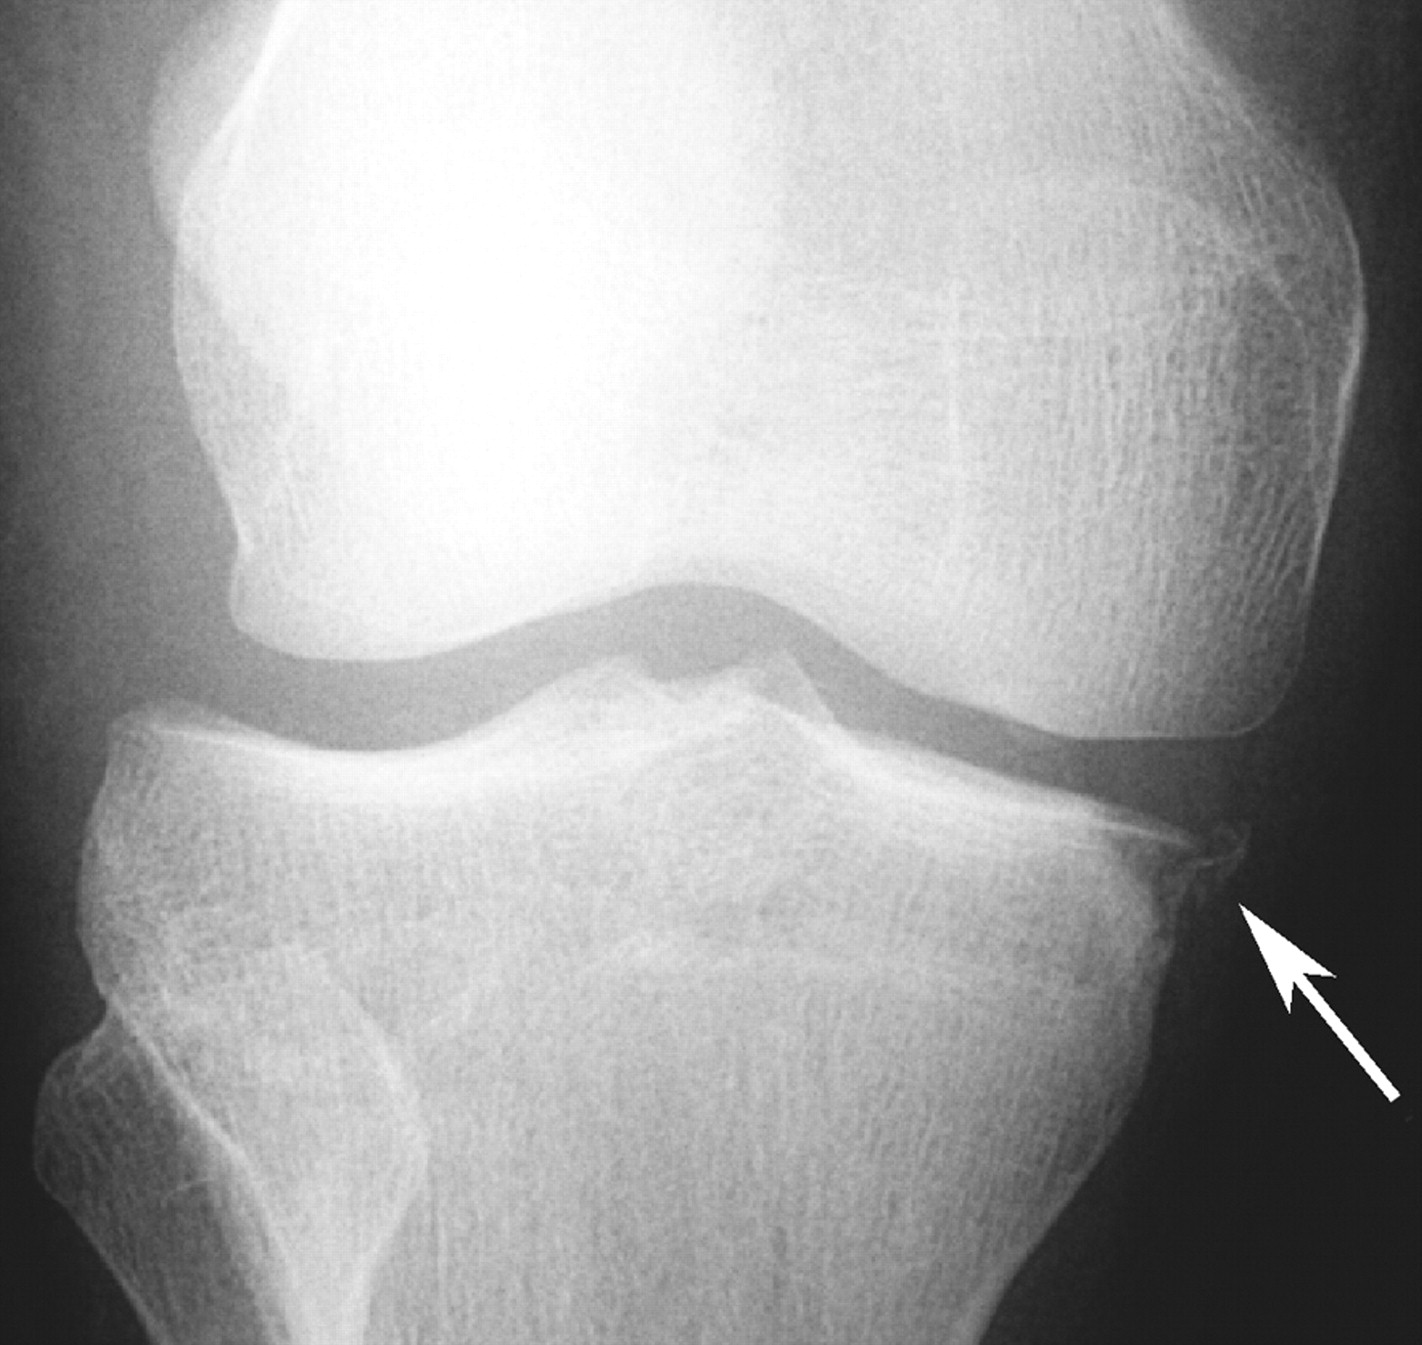

Segond Fracture

This is a very subtle "avulsion fracture of the tibia below the articular margin" caused by traction on the capsular or coronary ligaments. It is not possible to cause this fracture without first rupturing at least one of the major ligaments in the knee.

The classical description1 is limited to the lateral side where associated injuries include:-

Examples in order of increasing subtlety: -